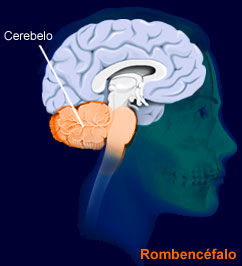

Hoy, vamos a agregar un ingrediente más, en este peculiar programa de cocina cerebral, una estructura similar a un guisante (algunos científicos hablan del formato de pera muy pequeña ó de San Juan), con un peso de 0.5 gramos, que se denomina científicamente glándula pituitaria (también conocida como hipófisis, “crecimiento inferior”) y que se aloja en un espacio óseo, la silla turca, del hueso esfenoides, situada en la base del cráneo, en la fosa cerebral media, que conecta con el hipotálamo a través del tallo pituitario o tallo hipofisario. La etimología es sumamente curiosa para comprender anatómicamente esta microestructura de extraordinaria importancia en las mujeres y hombres, por este orden. Pituitaria significa que contiene o segrega pituita, del latín “pituita”: secreción, fluido, moco, flema, formando parte de la medicina tradicional junto a los tres “humores” restantes: sangre, bilis amarilla y bilis negra. Es una superestructura del sistema endocrino dado que ejerce un control férreo sobre ocho glándulas endocrinas que explicamos a continuación.

Esta glándula está unida al hipotálamo a través de fibras nerviosas y está formada por tres secciones: el lóbulo anterior, que representa el 80% del peso de la glándula, el lóbulo intermedio y el lóbulo posterior. El lóbulo anterior produce la hormona de crecimiento, la prolactina, que estimula la producción de leche materna después de dar a luz, la adrenocorticotrópica (ACTH), que estimula las glándulas adrenales, la estimulante de la tiroides (TSH), que estimula la glándula tiroides, la folículo-estimulante (FSH), que estimula los ovarios y los testículos al igual que la luteinizante (LH), también presente.

El lóbulo intermedio, produce la hormona estimulante de melanocitos que controla la pigmentación de la piel. El lóbulo posterior, produce la hormona antidiurética (ADH), que aumenta la absorción de agua en la sangre por medio de los riñones. Igualmente, la oxitocina, que contrae el útero durante el parto y estimula la producción de la leche materna.

Esta supercentral hormonal cumple unas funciones determinantes en el ser humano. Louann Brizendine, la autora revelación sobre el cerebro femenino, sitúa la glándula pituitaria como sexta estructura que lo caracteriza: “produce las hormonas de la fertilidad, producción de leche y comportamiento de crianza. Ayuda a poner en marcha el cerebro maternal”. Además, en el salto de la pubertad se desencadena la propulsión de las células hipotalámicas y la niña-mujer comienza a experimentar cambios que ya se repetirán día a día, mes a mes hasta la menopausia, porque “la glándula pituitaria… salta a la vida cuando los frenos químicos se sueltan en las células hipotalámicas […]. Esta liberación celular dispara el sistema hipotalámico-pituitario-ovárico” (1). El conocimiento de esta realidad recurrente en la vida de la mujer debe ayudar a los hombres a respetar íntegramente estos ciclos vitales que producen desajustes vitales, por responsabilidad directa de la naturaleza al estar muy desarrollada esta glándula en la mujer en el lóbulo anterior de la misma (recuerdo que el peso específico de esta zona desarrolla el 80% de su función diaria y perfectamente programada). No ocurre lo mismo en el cerebro masculino, porque el balanceo hormonal no pasa tanta factura en la vida ordinaria. Si se conoce bien esta estructura, se respeta. Además, se pueden poner ejemplos rotundos de este “conocimiento” cerebral femenino, basados en una hormona bastante desconocida a nivel popular pero que juega un papel trascendental en la mujer y en las relaciones de pareja. Me refiero a la oxitocina, una hormona muy atractiva para el objeto de estas publicaciones.